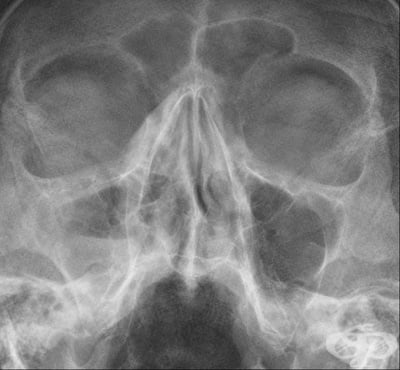

За поставяне на диагнозата остър синузит имат значение симптомите на пациента, лабораторните изследвания на кръвта, рентгенография на околоносните синуси, при необходимост и компютърна томография. При хроничен синузит е добре да се направи и микробиологично изследване. Болният трябва да отиде на л...

Синузит Възпалени синуси Синузит Симптоми при синузит Синузит Синузит Риноскопия Рентгенография максиларен синузит Компютърна томография етмоидакен синузит ЯМР синузит Одонтогенен синузит Лечение на синузит

СинузитВъзпалени синусиСинузитСимптоми при синузитСинузитСинузитРиноскопияРентгенография максиларен синузитКомпютърна томография етмоидакен синузитЯМР синузитОдонтогенен синузитЛечение на синузитЛечение на синузит